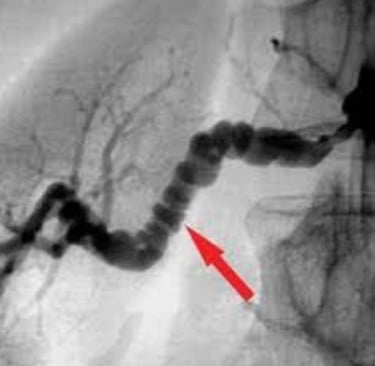

Onu tanımanın yolu, laboratuvar kağıtlarına değil, hastanın bacaklarına (Livedo) ve anjiyografisindeki o ürkütücü "tespih tanelerine" bakmaktır.

En karakteristik özelliği, damar duvarını zayıflatarak oluşturduğu mikro-anevrizmalardır. Anjiyografide bu anevrizmalar bir ip üzerine dizilmiş boncuklar gibi görünür (Rosary Sign).

Anjiyografide Mikroanevrizmalar: LR+ ∞ (sonsuz). Altın Standart. Böbrek veya mezenter (bağırsak) damarlarında tespih tanesi görünümü.